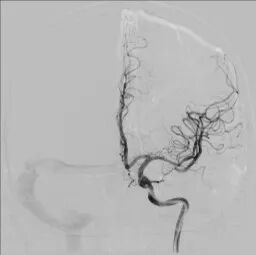

术后影像及检查

全脑及病变处不同体位造影:狭窄处成形好,未残余明显狭窄,左大脑中动脉主干及各分支显影好。

导丝怎么扩【载药时代 球扩天下】NOVA DES®颅内药物球扩支架在大脑中动脉重度狭窄中的应用——济南市第四人民医院使用体会一例!_https://www.jmylbn.com_新闻资讯_第13张

导丝怎么扩【载药时代 球扩天下】NOVA DES®颅内药物球扩支架在大脑中动脉重度狭窄中的应用——济南市第四人民医院使用体会一例!_https://www.jmylbn.com_新闻资讯_第14张